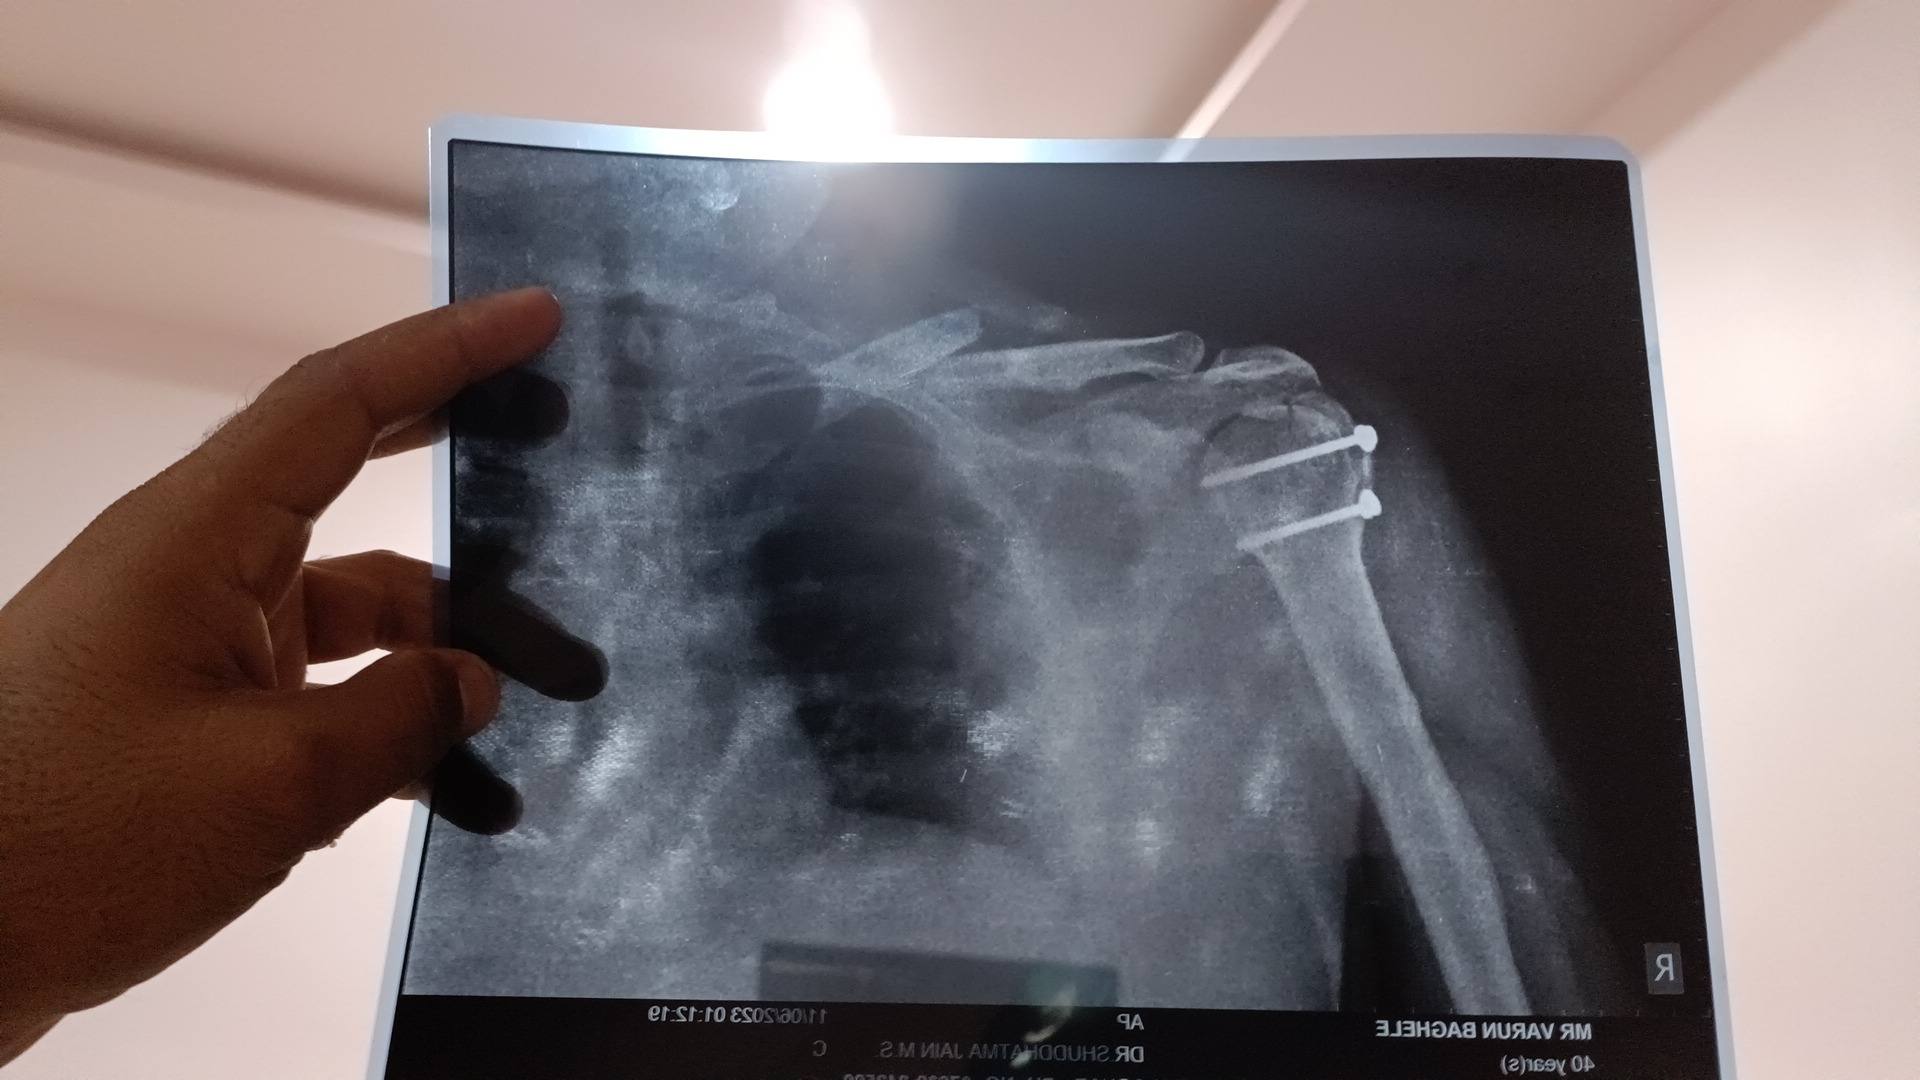

Cycercial facture

Need any operation

After 22 days Sir any problem